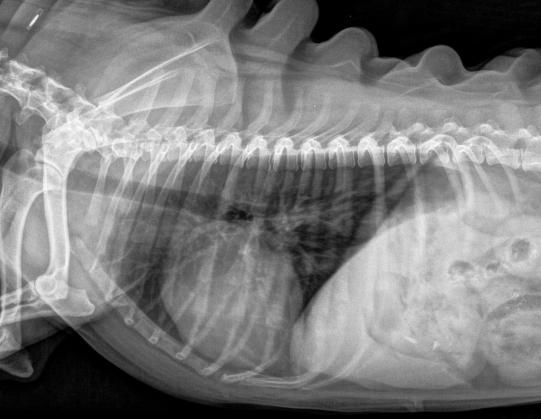

Eine Woche später wird die Lunge nochmals geröntgt - es sind glücklicherweise keine Hinweise auf eine Lungenentzündung zu sehen. Hingegen berichten die Besitzer, dass der Hund weiterhin (wie offenbar schon seit längerer Zeit) alle paar Tage erbricht - der Verdacht, dass sich im Magen ein weiterer, älterer Fremdkörper befinden könnte, bleibt so bestehen.